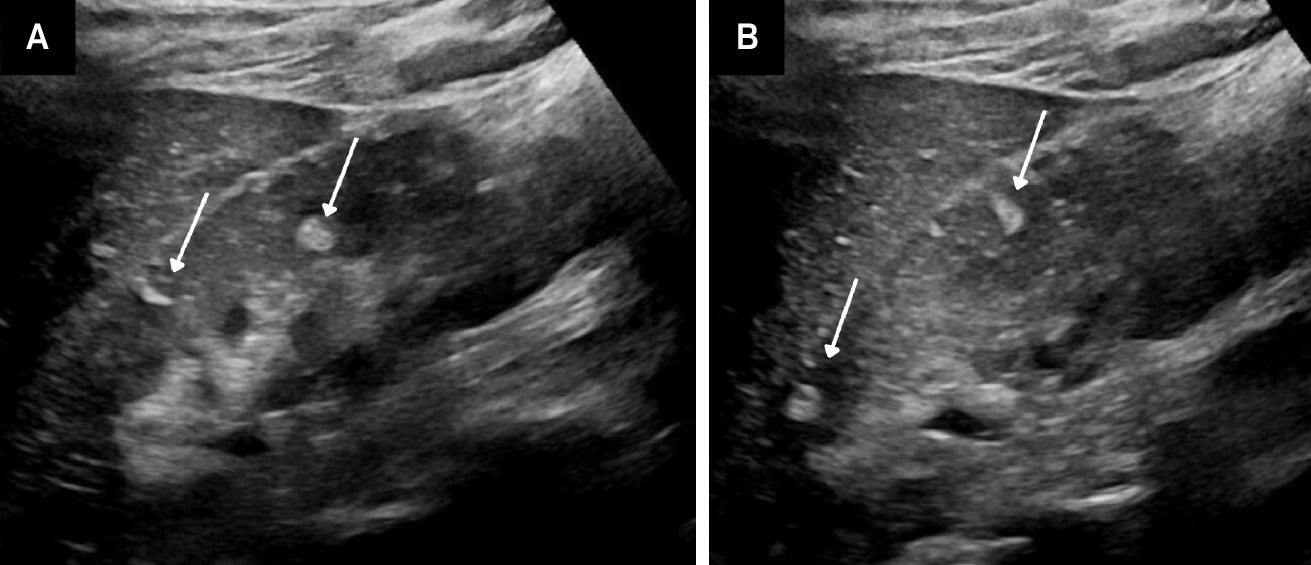

TS is a genetic disorder characterized by the presence of noncancerous tumors in multiple organs. Renal AML, usually the classic, fat-containing type, occurs in up to 75% of patients with TS. These tumors, which may occur at any age, are often multiple and bilateral ( Figure 3 ) and tend to enlarge with age ( Figure 4 ). Nonclassic subtypes, including fpAML, AML with epithelial cysts, and epithelioid AML, occur more frequently in TS than sporadic AML.4, 5 Close follow-up may be indicated. AMLs in TS tend to be larger and hemorrhage more frequently, necessitating treatment, often with catheter-based interventions for larger tumors (>4 cm) or those that have hemorrhaged.

Angiomyolipomas (AMLs) on US. Adolescent with tuberous sclerosis and multiple echogenic AMLs (arrows) within the right kidney (A). Similar masses were seen in the left kidney (B).